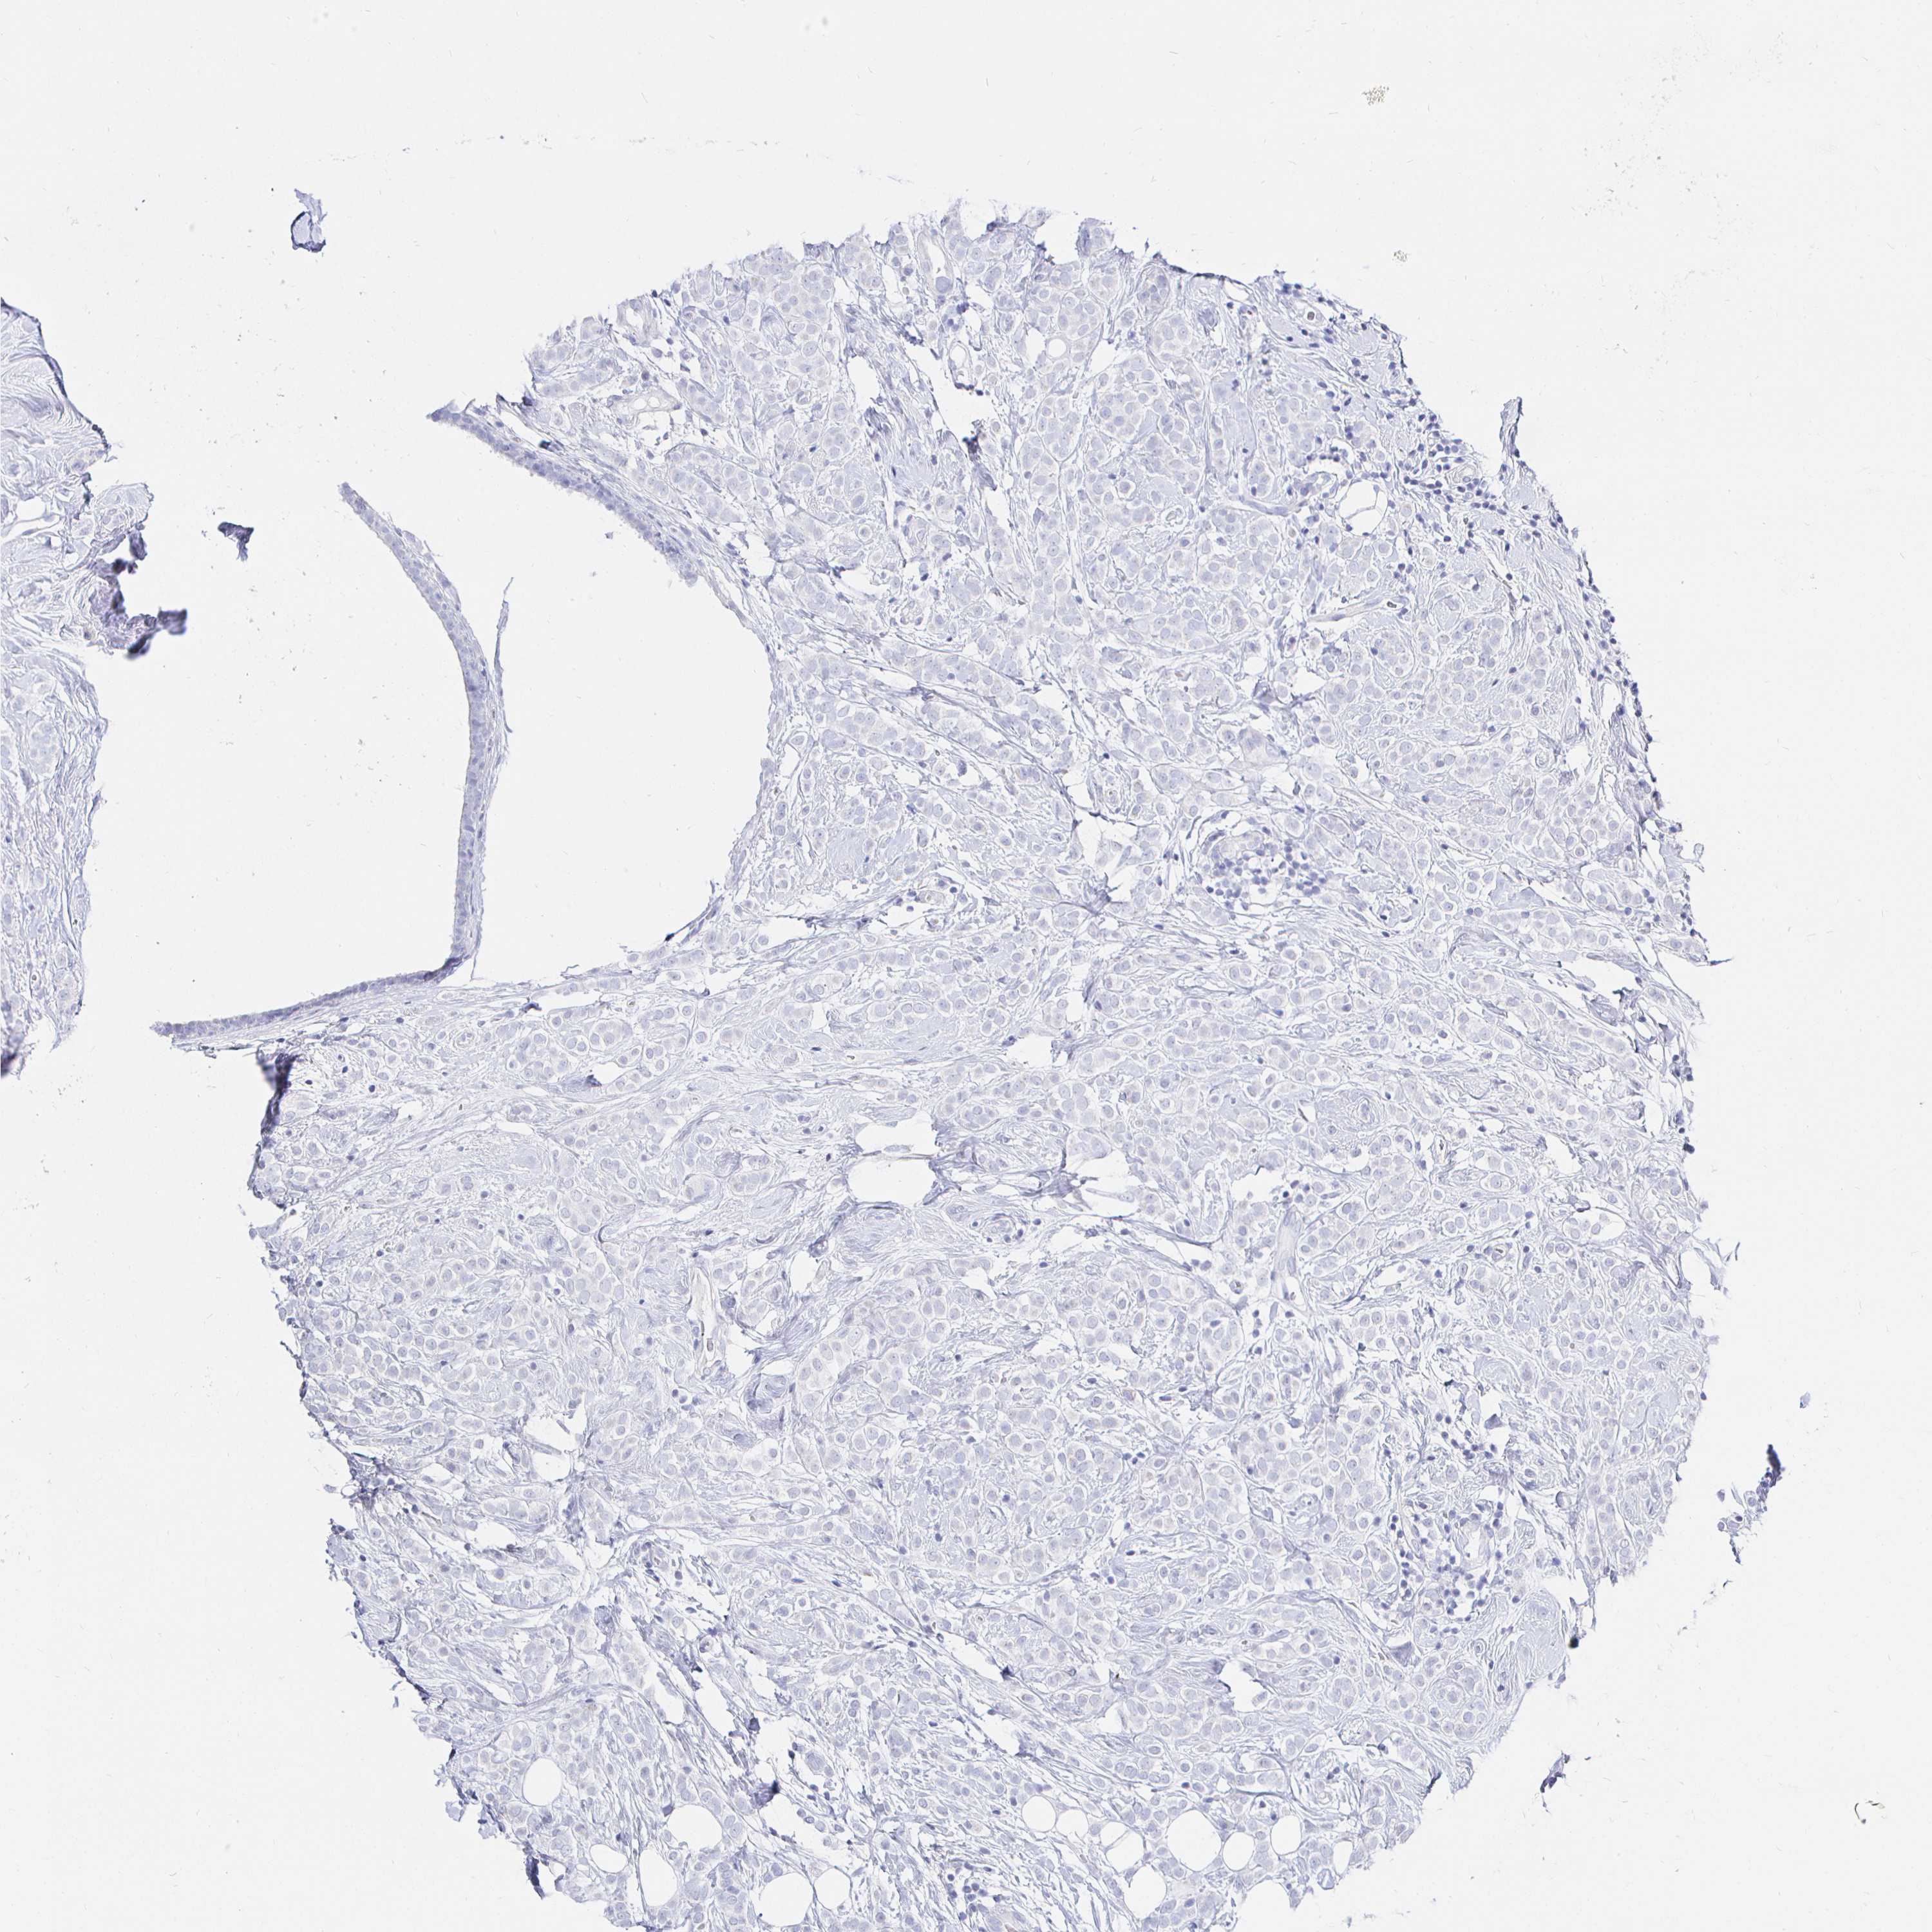

BRCA TCGA BRCA VALIDATION PROTEIN EXPRESSION

Breast cancer

Human cancer